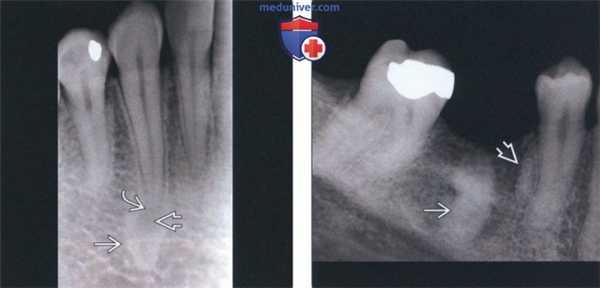

(Слева) На периапикальной рентгенограмме определяется склерозирующий остеит в области корней первого моляра нижней челюсти слева. Определяется также рарефицирующий остеит в области корней зуба. Обратите внимание на остеосклероз, «смешивающийся» с окружающей нормальной костью.

(Справа) На периапикальной рентгенограмме определяется хорошо отграниченное однородное затемнение с неровными краями у вершины первого моляра нижней челюсти справа. Пространства периодонтальной связки и твердые пластинки не изменены. (Слева) На периапикальных рентгенограммах нижних передних зубов определяется прогрессирующая периапикальная костная дисплазия. На рентгенограмме справа, выполненной через семь лет после левой, определяется постепенное нарастание минерализации очагов.

(Справа) На периапикальной рентгенограмме определяется луковицеобразное расширение кор ня с сохранением твердой пластинки и пространств ПДС, сопоставимое с гиперцементозом.